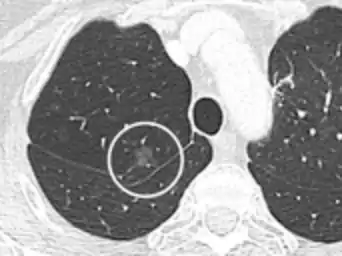

CT image showing ground-glass nodule (circled).

Pre-malignant or malignant causes of nodular GGOs include adenocarcinoma, adenocarcinoma in situ, and atypical adenomatous hyperplasia (AAH). One large review study found that 80% of nodular GGOs which were present on repeated CT imaging represented either pre-malignant or malignant growths. Differentiating between pre-malignancy and malignancy on the basis of CT alone can pose a challenge to radiologists; however, there are several features that that are indicative of pre-malignant nodules. AAH is a pre-malignant cause of nodular GGO and is more commonly associated with lower attenuation on CT and smaller nodule size (<10 mm) compared to adenocarcinoma.[11] In addition, AAH often lacks the solid features and spiculated appearance that are often associated with malignant growths.[10] In contrast, as adenocarcinoma becomes invasive it will more often cause retraction of adjacent pleura and may show an increase in vascular markings. Nodules >15 mm almost always represent an invasive adenocarcinoma.[10][11]